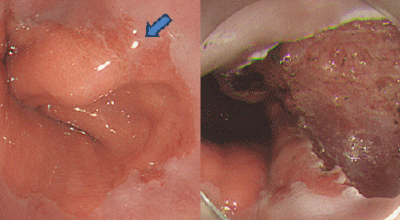

식도암은 다른암에 비해 사망률이 아주 높은 암이랍니다. 초기 발견 시에는 예후가 매우 좋지만, 2,3기에 발견될 시에는 사망률이 급격히 오르게 돼요. 다만 초기에는 증상이 거의 없으므로 문제가 됩니다. 초기에 관찰되는 경우는 내시경을 통한 방법말고는 거의 없다고 합니다. 그러기에 주기적인 내시경은 필수겠죠.

안타깝지만 식도암 초기증상은 잘 느끼지 못합니다. 하지만 방법은 있어요. 그것은 바로 위 내시경 검사를 받는 것으로 보입니다. 위 내시경 검사를 받을 때 식도를 거쳐서 내시경 검사를 하므로 우리는 반드시 2년에 한번씩, 나이가 50대가 넘었다면 1년에 한번씩 내시경 검사를 받아야 합니다.